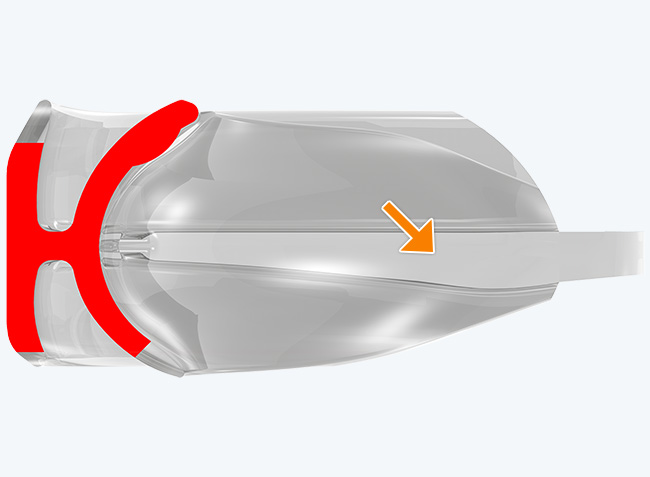

The TMJ Appliance®, which does not require any special fitting, is designed to act as an initial diagnostic and treatment tool for TMJ disorder. It works by decompressing the temporomandibular joint (TMJ), helps to correct mouth breathing and tongue posture habits, as well as limits bruxing. The TMJ Appliance® achieves TMJ disorder symptom relief immediately by alleviating pressure on the TMJ and relaxes the muscles around the jaw and neck.

The TMJ Appliance® treats both intracapsular and extracapsular disorders—TMJ clicking and pain (intracapsular) as well as pain referred from the craniomandibular muscles (extracapsular).